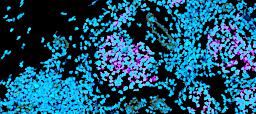

Pancreatic ductal adenocarcinoma is a lethal disease with limited treatment options and poor survival. We studied 83 spatial samples from 31 patients (11 treatment-naïve and 20 treated) using single-cell/nucleus RNA sequencing, bulk-proteogenomics, spatial transcriptomics and cellular imaging. Subpopulations of tumor cells exhibited signatures of proliferation, KRAS signaling, cell stress and epithelial-to-mesenchymal transition. Mapping mutations and copy number events distinguished tumor populations from normal and transitional cells, including acinar-to-ductal metaplasia and pancreatic intraepithelial neoplasia. Pathology-assisted deconvolution of spatial transcriptomic data identified tumor and transitional subpopulations with distinct histological features. We showed coordinated expression of TIGIT in exhausted and regulatory T cells and Nectin in tumor cells. Chemo-resistant samples contain a threefold enrichment of inflammatory cancer-associated fibroblasts that upregulate metallothioneins. Our study reveals a deeper understanding of the intricate substructure of pancreatic ductal adenocarcinoma tumors that could help improve therapy for patients with this disease.